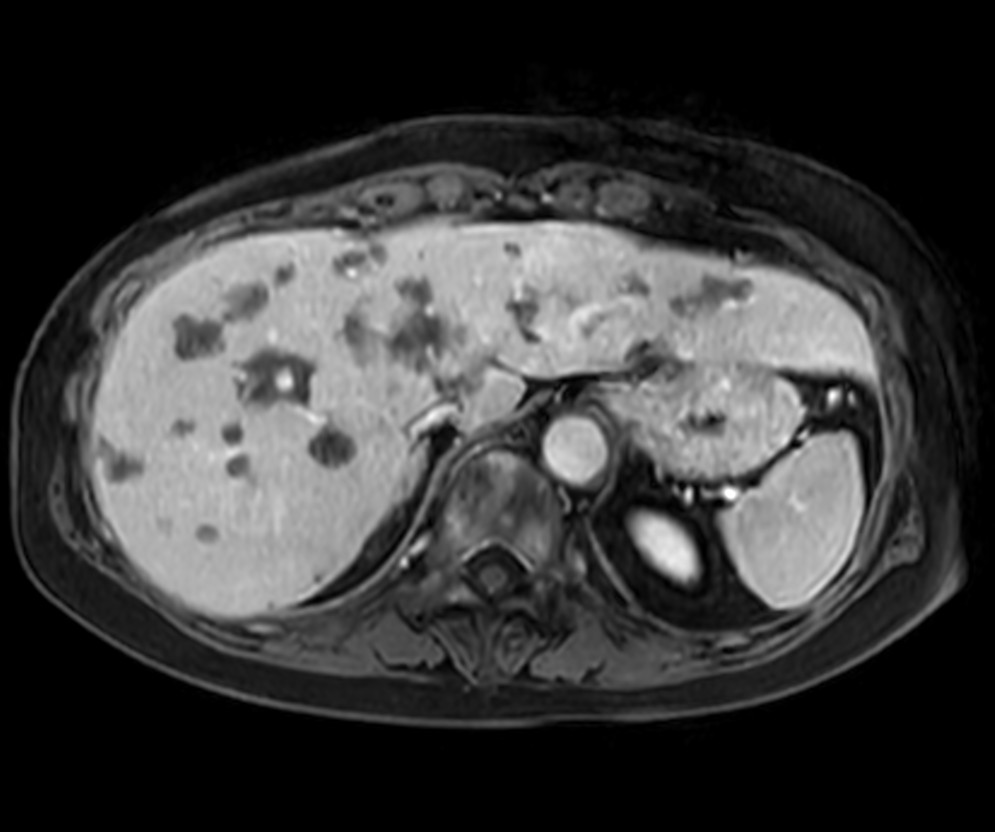

Axial T2w SSh